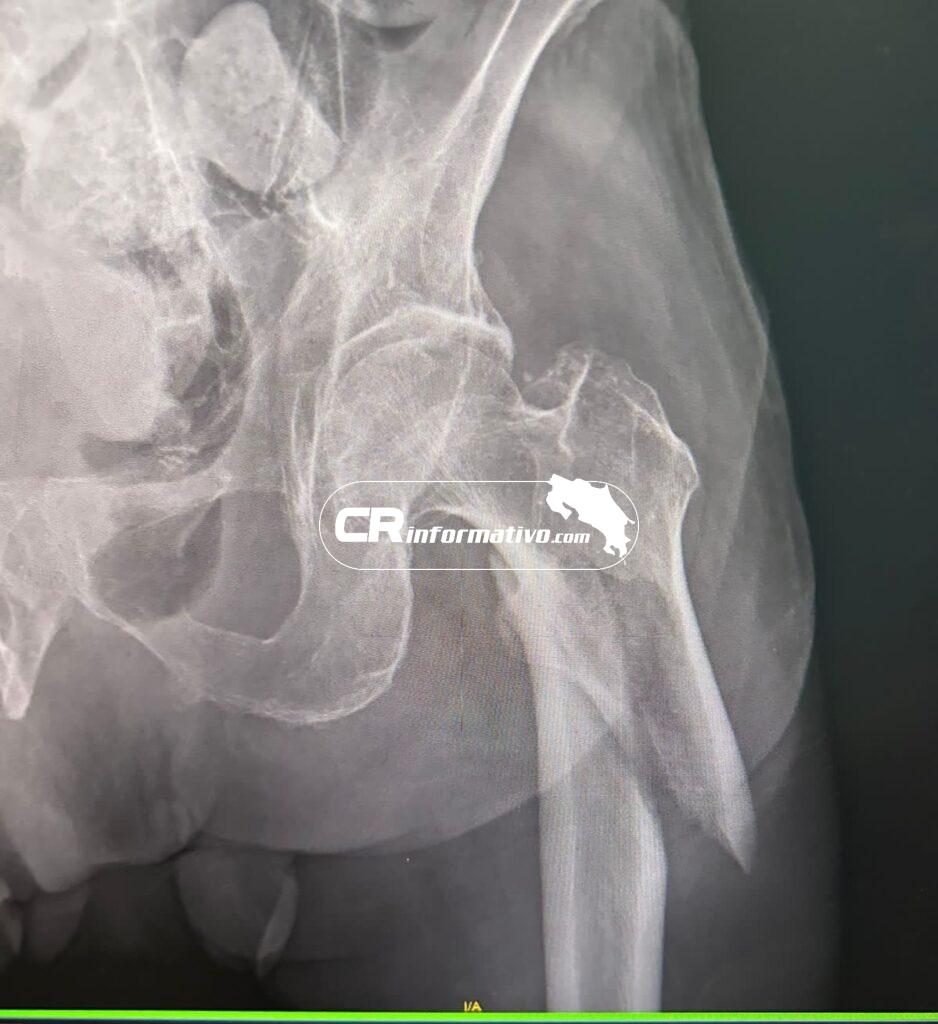

“La cirugía duró aproximadamente una hora y treinta minutos. Le colocamos un clavo intramedular que entra por el fémur y se fija con dos clavos. Para el tipo de fractura que tenía el paciente este era el procedimiento idóneo”, explicó el galeno.